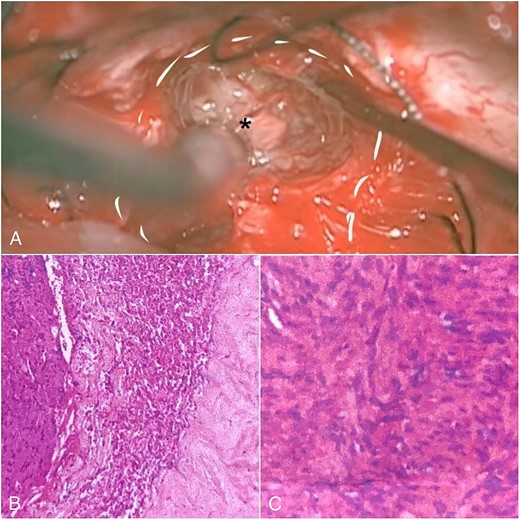

We carefully identified the tumor border’s inferior pole and used a surgical cottonoid to mark the border between the lower cranial nerve. This technique will help us as a mark while performing tumor resection to prevent lower cranial nerve injury. The tumor removal process was performed piece by piece using micro scissors to better visualize the CPA region, thus minimizing brain retraction and safely dissecting the tumor from the brainstem. Anatomically, the facial nerve has already been severely disrupted by the tumor, and the capsule has adhered to the facial nerve with moderate preoperative facial nerve dysfunction. Then, we decided to leave some tumors surrounding the nerve fibers to prevent anatomical injury of the facial nerve. Meticulous dissection around the tumor using intraoperative monitoring (IOM) was performed to preserve the facial nerve. Drilling the internal auditory canal (IAC) using a high-speed drill is mandatory as removing the intrameatal part of the dumbbell schwannoma should start from normal nerve fibers. Resection was continued to detach the tumor from the lower cranial nerve and brainstem (Fig. 2A). Duraplasty was done, and the bone flap was placed back.

Intraoperative view and histopathological feature. (A) After debulking of the tumor, IAC was opened, and the intrameatal globular part (asterisk) could be appreciated and resected. (B) Histopathological findings show tumor cells with blood vessel proliferation that consist of collagen. (C) Schwann cells mixed with neuroma cells making a palisade-shaped structure.

The histopathological finding shows the characteristics of a cystic vestibular schwannoma (Fig. 2B and C). Postoperative imaging evaluation using a computed tomography scan revealed no intracranial hemorrhage or hydrocephalus. On the sixth month of evaluation, the patient could do a regular activity without any significant complaints. Postoperative imaging evaluation showed a residual mass surrounding the facial nerve (Fig. 1D–F). After a discussion with the patient, we planned to observe this lesion as it did not cause any significant symptoms.